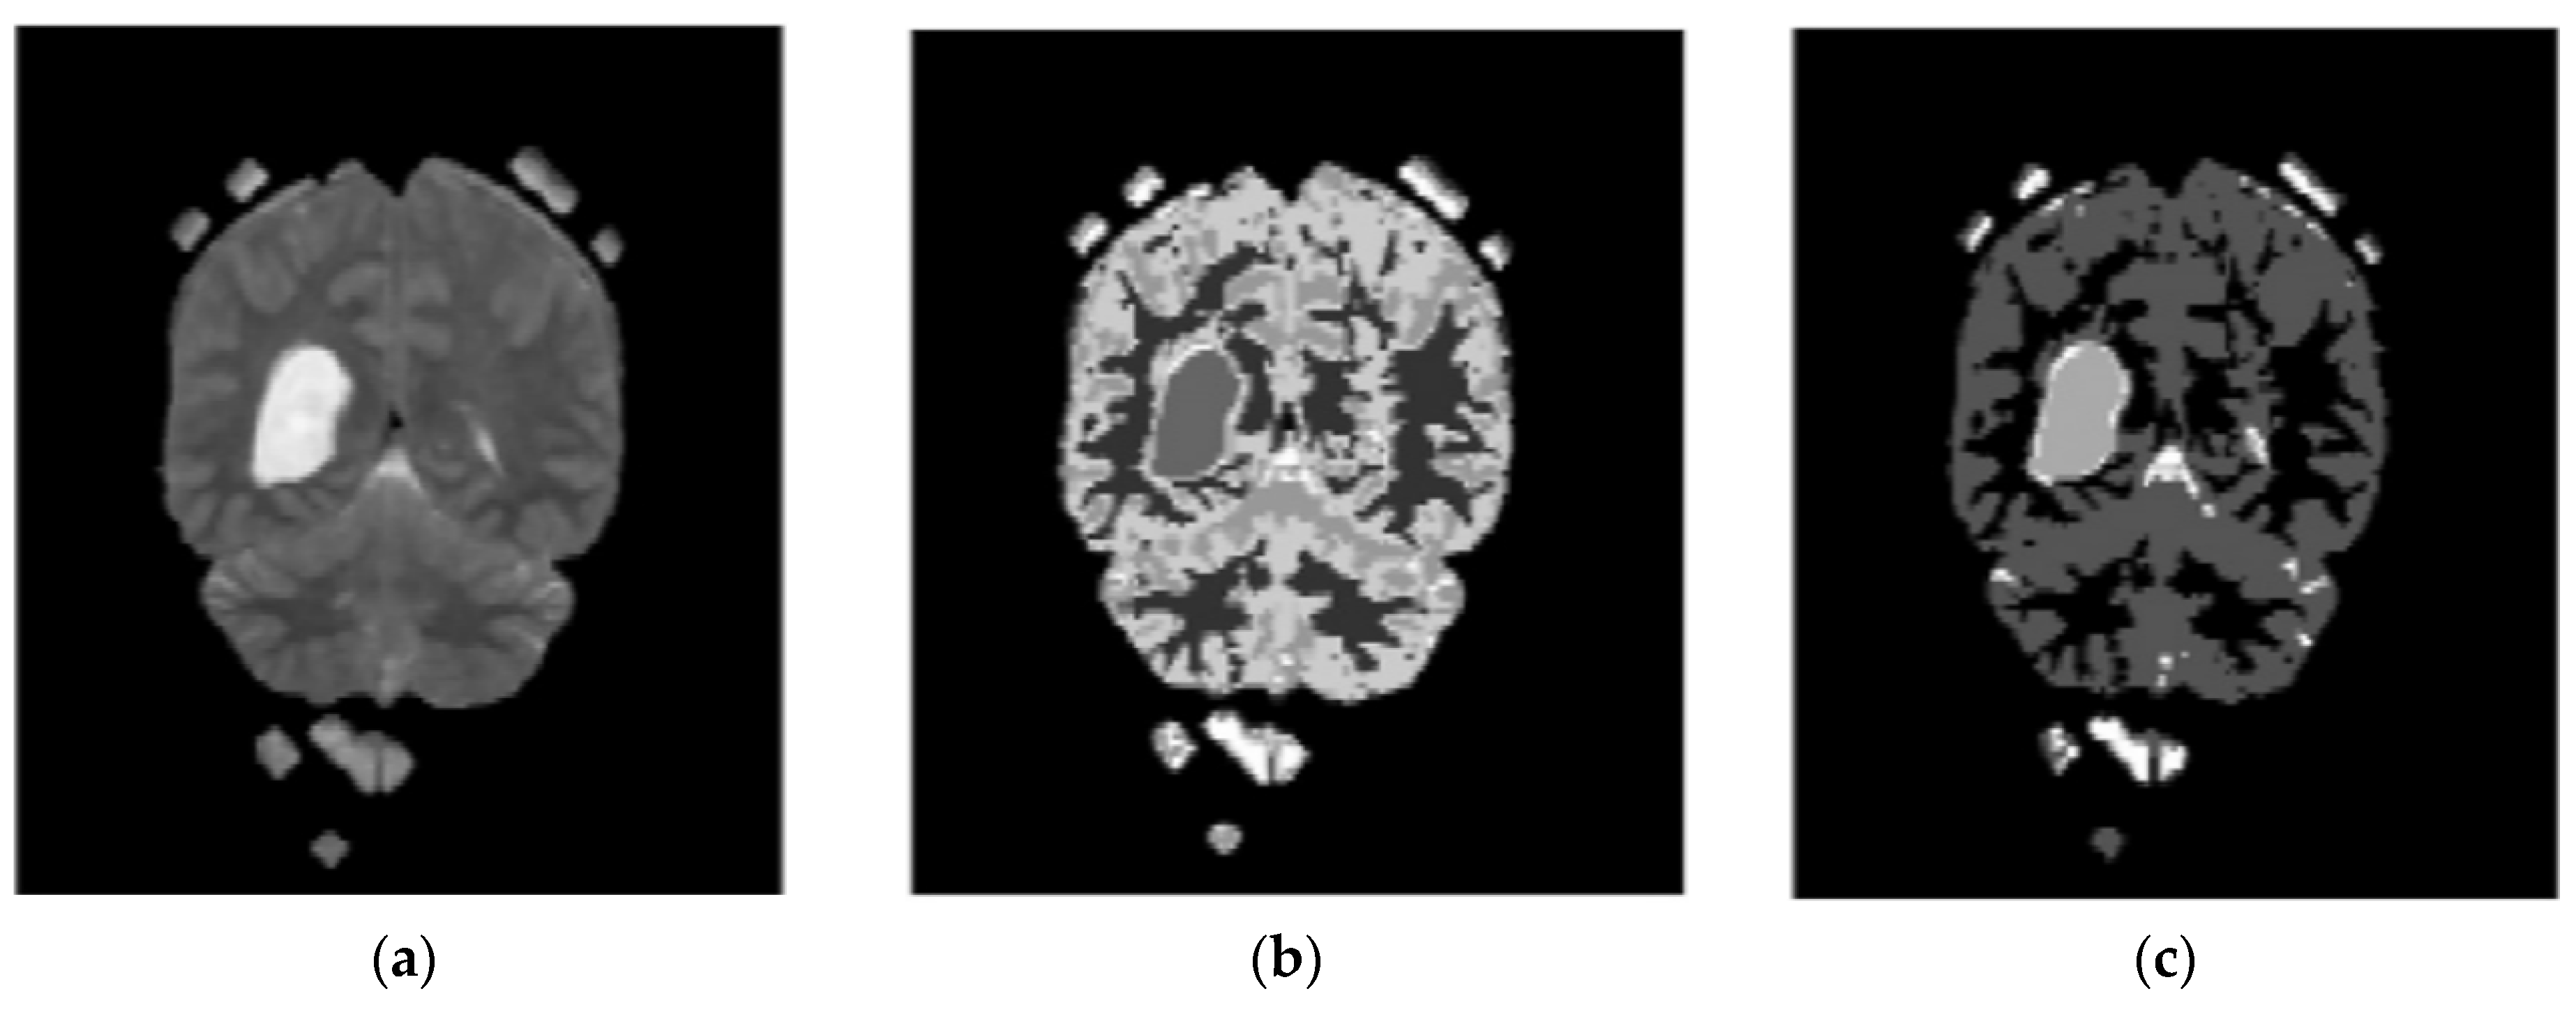

3.2. Stage 2: Segmentation—Enhanced Fuzzy C-Means Clustering

3.3. Stage 3: Feature Extraction—Local Binary GLCM